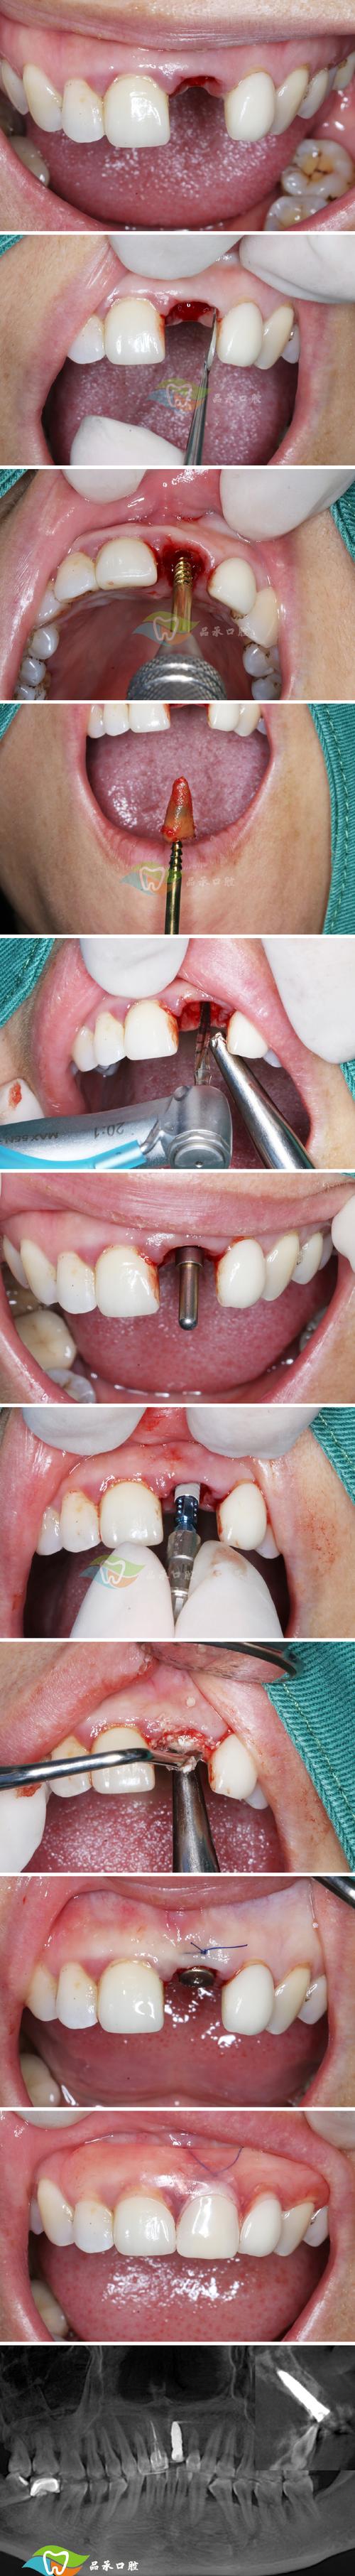

| 拔牙与窝洞预备 | 拔除患牙,彻底清创拔牙窝,去除炎症组织,修整骨壁 | 尽量保护牙槽骨壁完整性,避免过度搔刮,保留牙槽间隔,为种植体提供初期稳定性 |

| 种植体植入 | 选择合适直径、长度的种植体,植入拔牙窝,确保种植体尖端位于牙槽骨 cortical 下3-5mm | 种植体与骨壁紧密贴合,初期稳定性良好(扭矩≥35N·cm),避免邻牙损伤 |

| GBR(引导骨再生) | 若骨量轻微不足,可植入骨粉、骨膜,促进骨再生 | 严格隔湿,防止骨粉移位,确保生物膜覆盖骨缺损区 |

| 缝合与术后处理 | 无张力缝合拔牙创口,术后拍摄X光片确认种植体位置 | 嘱患者术后24小时内避免刷牙、漱口,服用抗生素预防感染,避免患侧咀嚼 |

术后需定期复查(术后1周、1个月、3个月),观察骨结合情况,一般3-6个月后,若种植体与骨组织结合良好(通过X光片或动度检测确认),可进行二期手术安装基台,再制作并佩戴牙冠,完成最终修复。